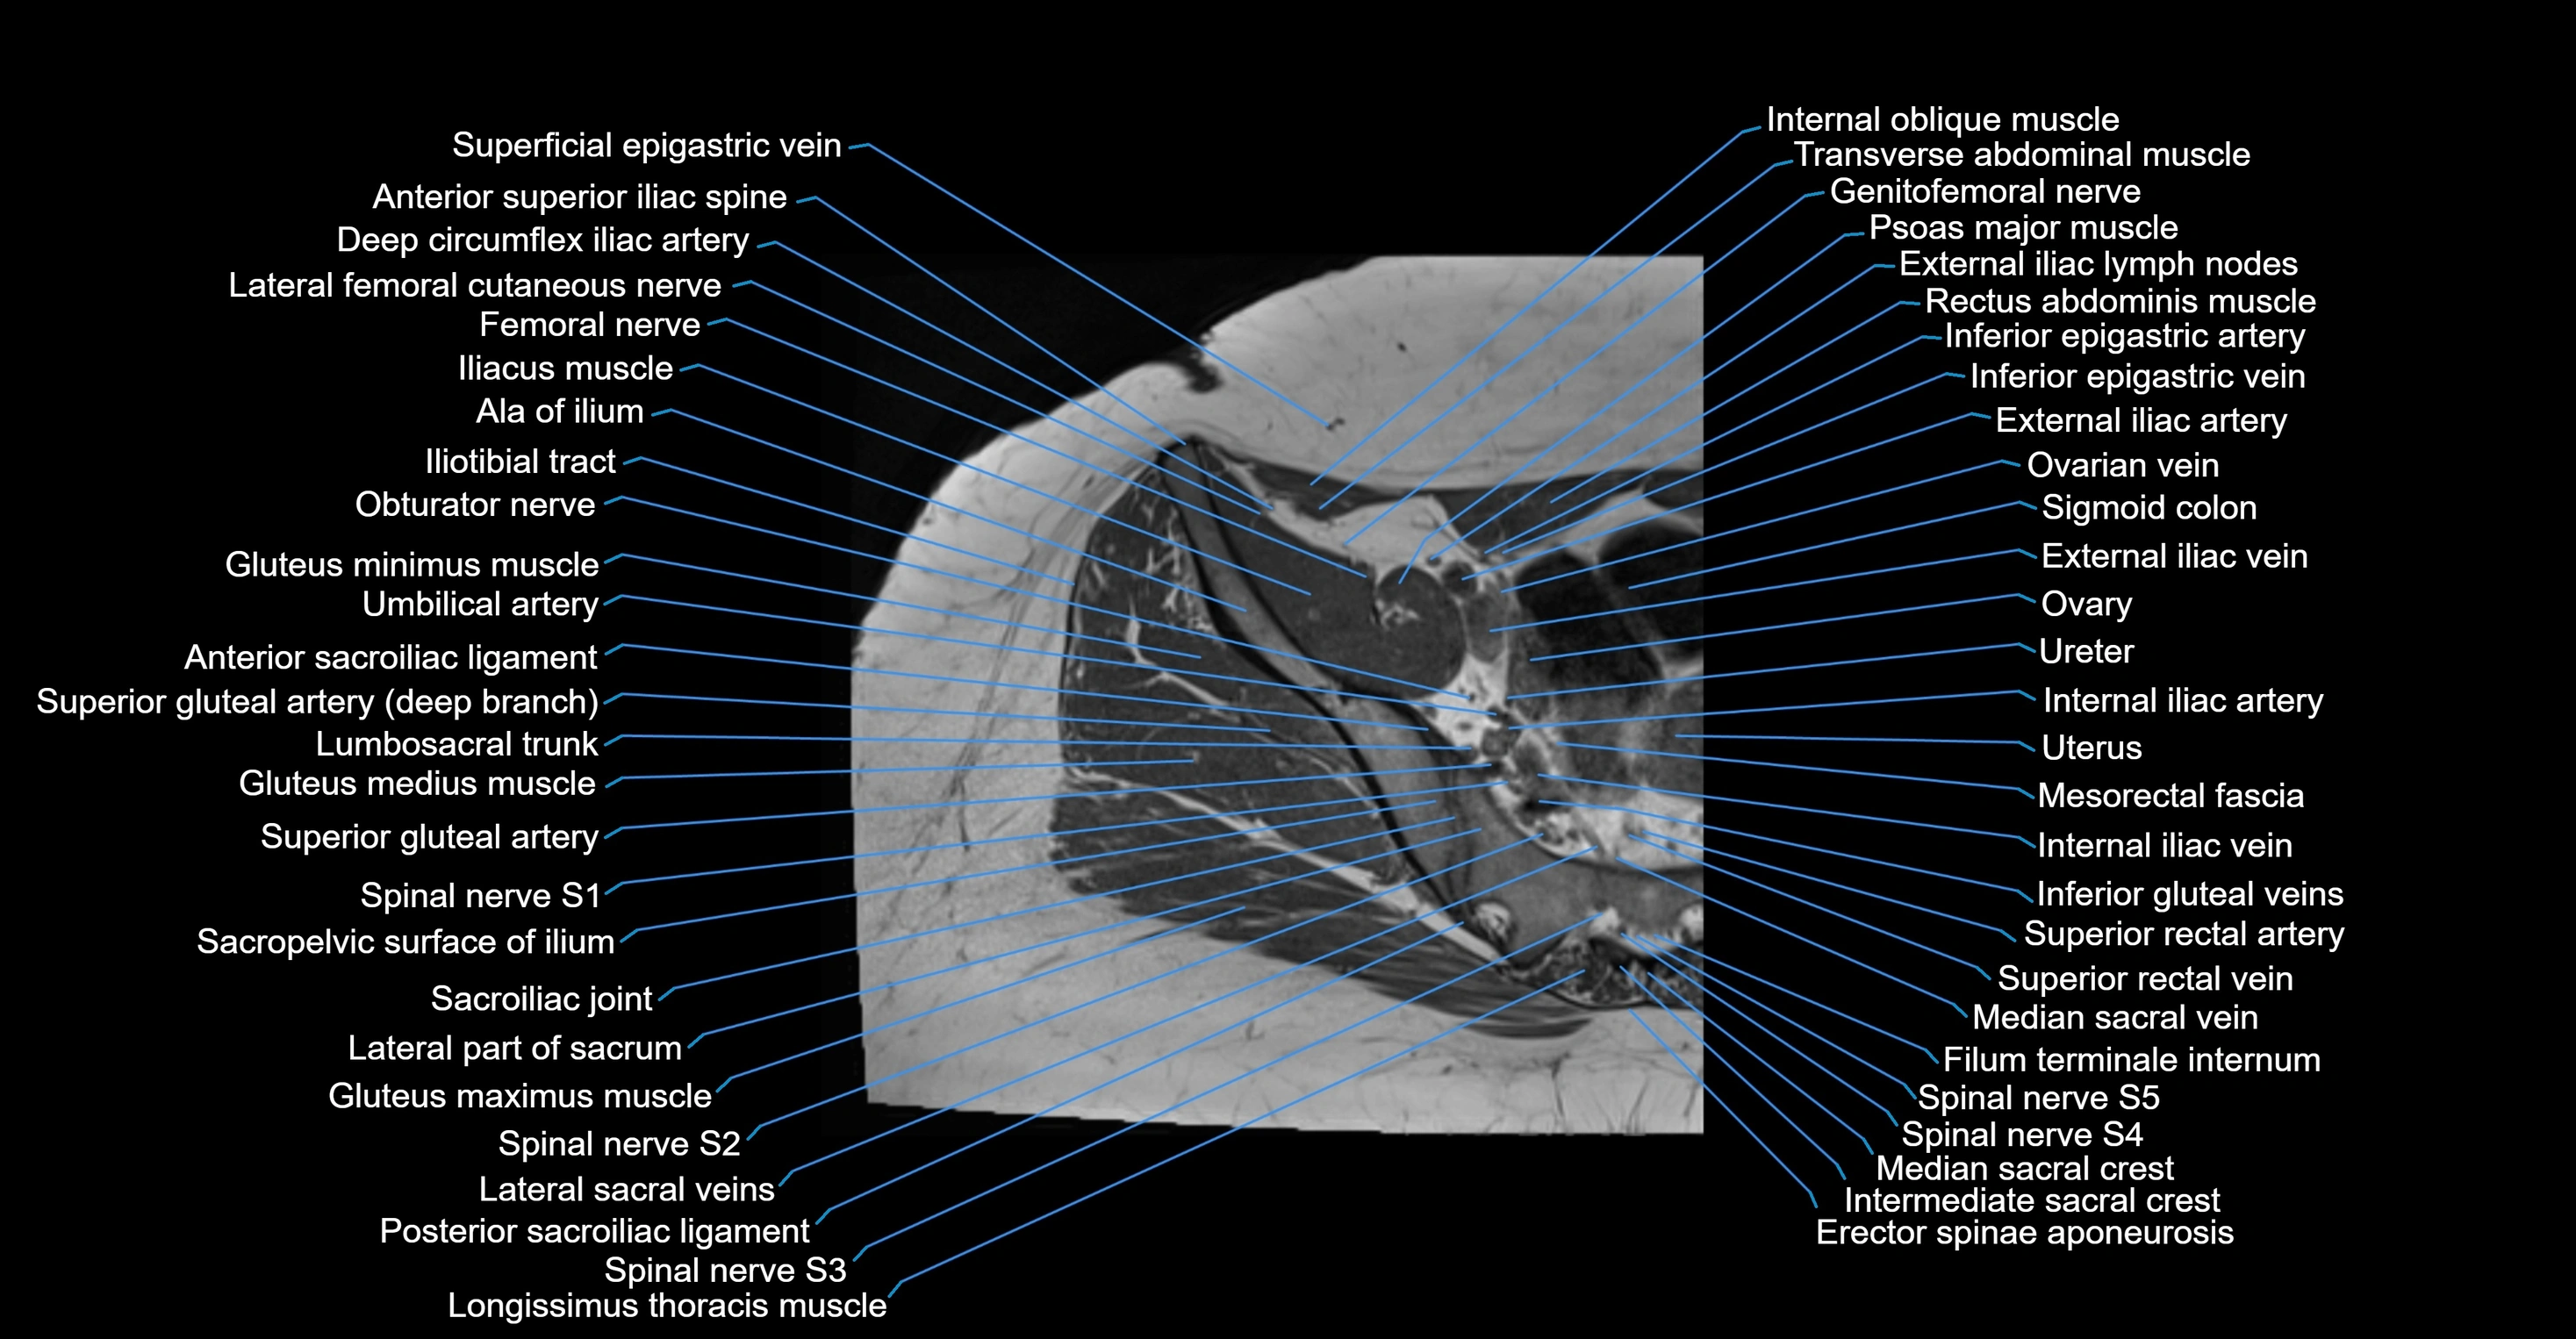

- Anterior sacroiliac ligament

- Anterior superior iliac spine

- Deep circumflex iliac artery

- External iliac artery

- External iliac vein

- Femoral nerve

- Genitofemoral nerve

- Gluteus maximus muscle

- Gluteus medius muscle

- Gluteus minimus muscle

- Iliotibial tract

- Ilium bone

- Inferior epigastric artery

- Inferior epigastric veins

- Internal iliac artery

- Lateral part of sacrum

- Lateral sacral vein

- Lumbosacral trunk

- Median sacral crest

- Median sacral vein

- Mesorectal fascia

- Sacroiliac joint

- Spinal nerve S1

- Spinal nerve S2

- Spinal nerve S3

- Spinal nerve S4

- Spinal nerve S5

- Superior gluteal artery

- Superior rectal vein

- Umbilical artery

- Uterus